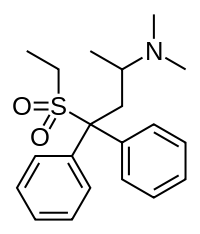

Others

- Viminol